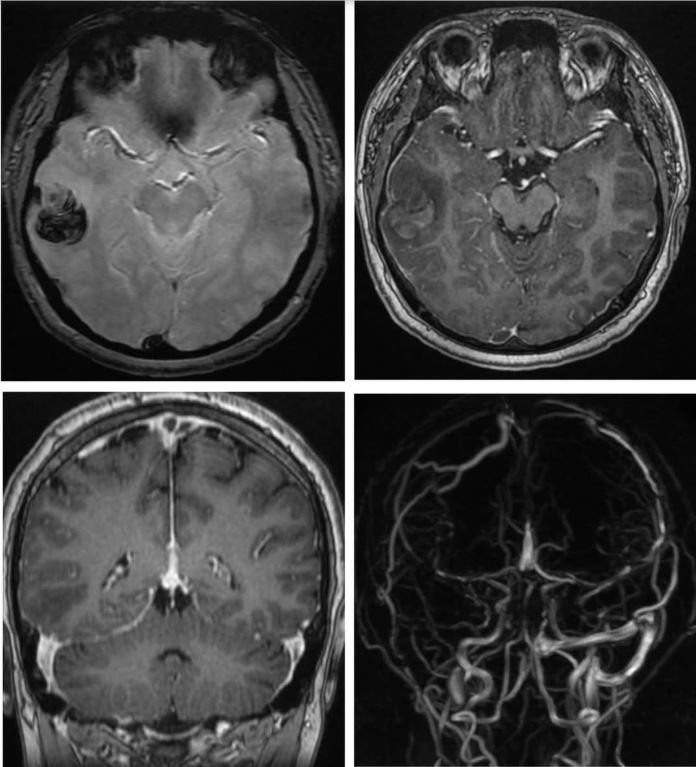

Phó Giáo sư, Tiến sĩ, bác sĩ Nguyễn Huy Thắng, Phó Chủ tịch Hội Đột quỵ Việt Nam, Trưởng Khoa Bệnh lý mạch máu não, Bệnh viện Nhân dân 115 Thành phố Hồ Chí Minh cho biết, nam thanh niên 22 tuổi, quê Cà Mau nhập viện trong tình trạng đau đầu dữ dội. Hình ảnh chụp CT scan cho thấy, bệnh nhân bị xuất huyết não.

Khi khảo sát thêm bằng cộng hưởng từ, các bác sĩ ghi nhận có huyết khối tại nhiều vị trí trong hệ thống tĩnh mạch não. Tìm hiểu kỹ về bệnh sử, người bệnh có thói quen hút shisha thường xuyên và ngày càng tăng dần trong suốt một năm qua. Sau khi được chẩn đoán và điều trị kịp thời, các bác sĩ đã giúp người bệnh hồi phục hoàn toàn.

Hình ảnh não của nam thanh niên bị xuất huyết. (Ảnh: BSCC).